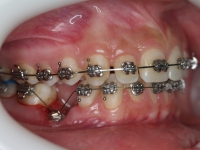

Premolar mandibular incluido + fenestración

45 incluido